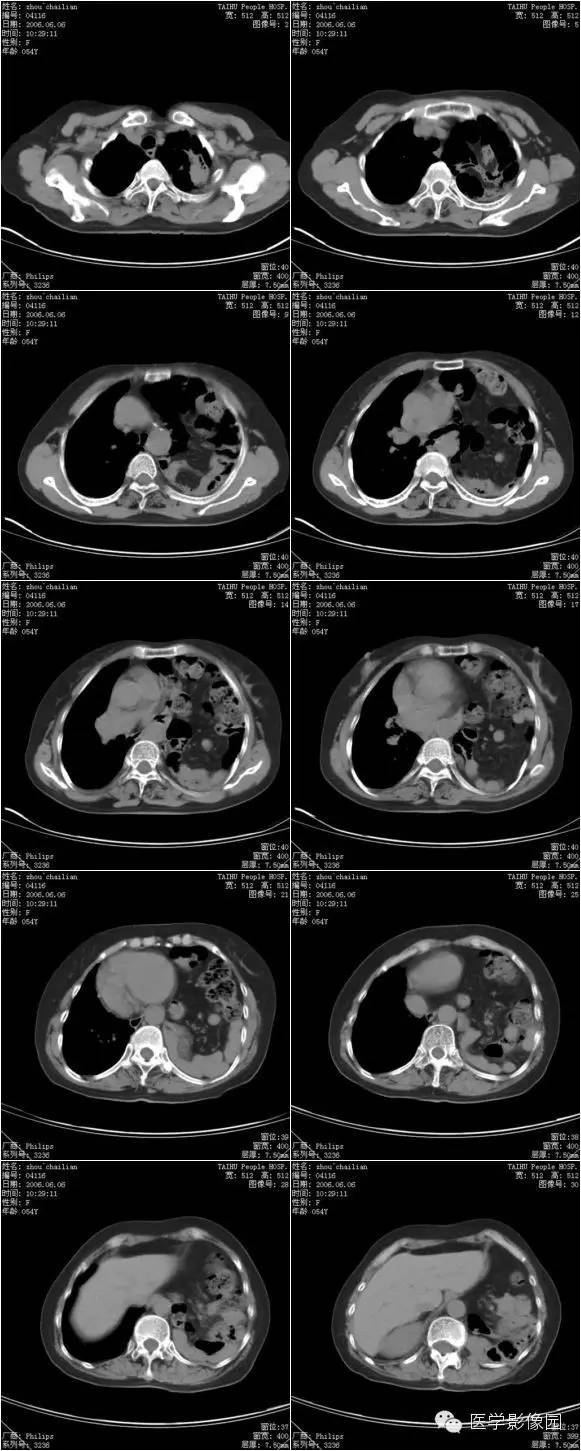

膈疝1例X线及CT影像表现

膈疝的形成除先天性膈肌融合部缺损和薄弱点外,还与下列因素有关:

①胸腹腔内的压力差异和腹内脏器的活动度;各种引起腹内压力增高的因素如弯腰、排便困难和怀孕等均可促使腹内脏器经膈肌缺损和薄弱部进入胸内。

②随着年龄增长,膈肌肌张力减退和食管韧带松弛,使食管裂孔扩大,贲站或胃体可以经过扩大的食管裂孔突入后纵隔。

③胸部外伤尤其胸腹联合伤引起膈肌破裂。